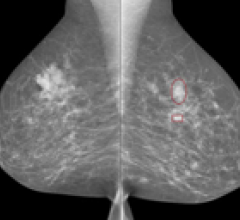

Parascript LLC announced a new partnership with Volpara Solutions, creator of Volpara Density automated breast density assessment software. Independent research has associated an increased risk of cancer for patients with high breast density, which can also make cancer harder to detect on conventional mammograms. Together, Parascript AccuDetect CAD (computer-aided detection) and VolparaDensity provide complementary early cancer detection solutions.

March 5, 2012 —Parascript LLC announced the latest version of its computer-aided detection (CAD) technology for mammography. AccuDetect 6.1 offers radiologists continued improvements in sensitivity and specificity in detecting suspicious lesions on mammograms.

November 30, 2011 –– Parascript, the image analysis and pattern recognition technology provider, announced the release of AccuDetect 5.0, the next generation of its computer-aided detection (CAD) software, aimed at helping radiologists improve breast cancer detection. AccuDetect 5.0 makes significant performance improvements over its predecessor and further reduces the potential for false-positive rates when detecting suspicious lesions on mammograms.

November 17, 2010 — AccuDetect 4.0 computer-aided detection (CAD) software has been released. It features performance improvements and a greater potential for lowering false-positive rates when detecting suspicious lesions on mammograms as compared to the previous version of the product.